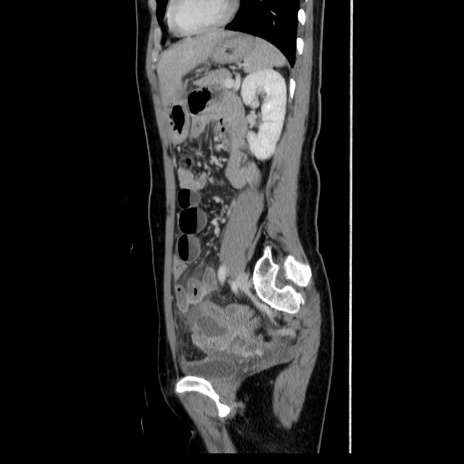

症例39(矢状断像)

【症例】40歳代女性

【主訴】上下腹部痛

【現病歴】2日目から下腹部痛あり。夜間は痛みで眠れなかった。昨日より上腹部痛と下痢が出現。臥位で痛みは軽快したため、休んでいた。本日になって臥位でも立位でも痛みが強くなってきたため救急要請。

【既往歴】子宮内膜症

【身体所見】部:平坦・軟、左上下腹部に圧痛あり、反跳痛あり。

【データ】WBC 21800、CRP 26.78

CT